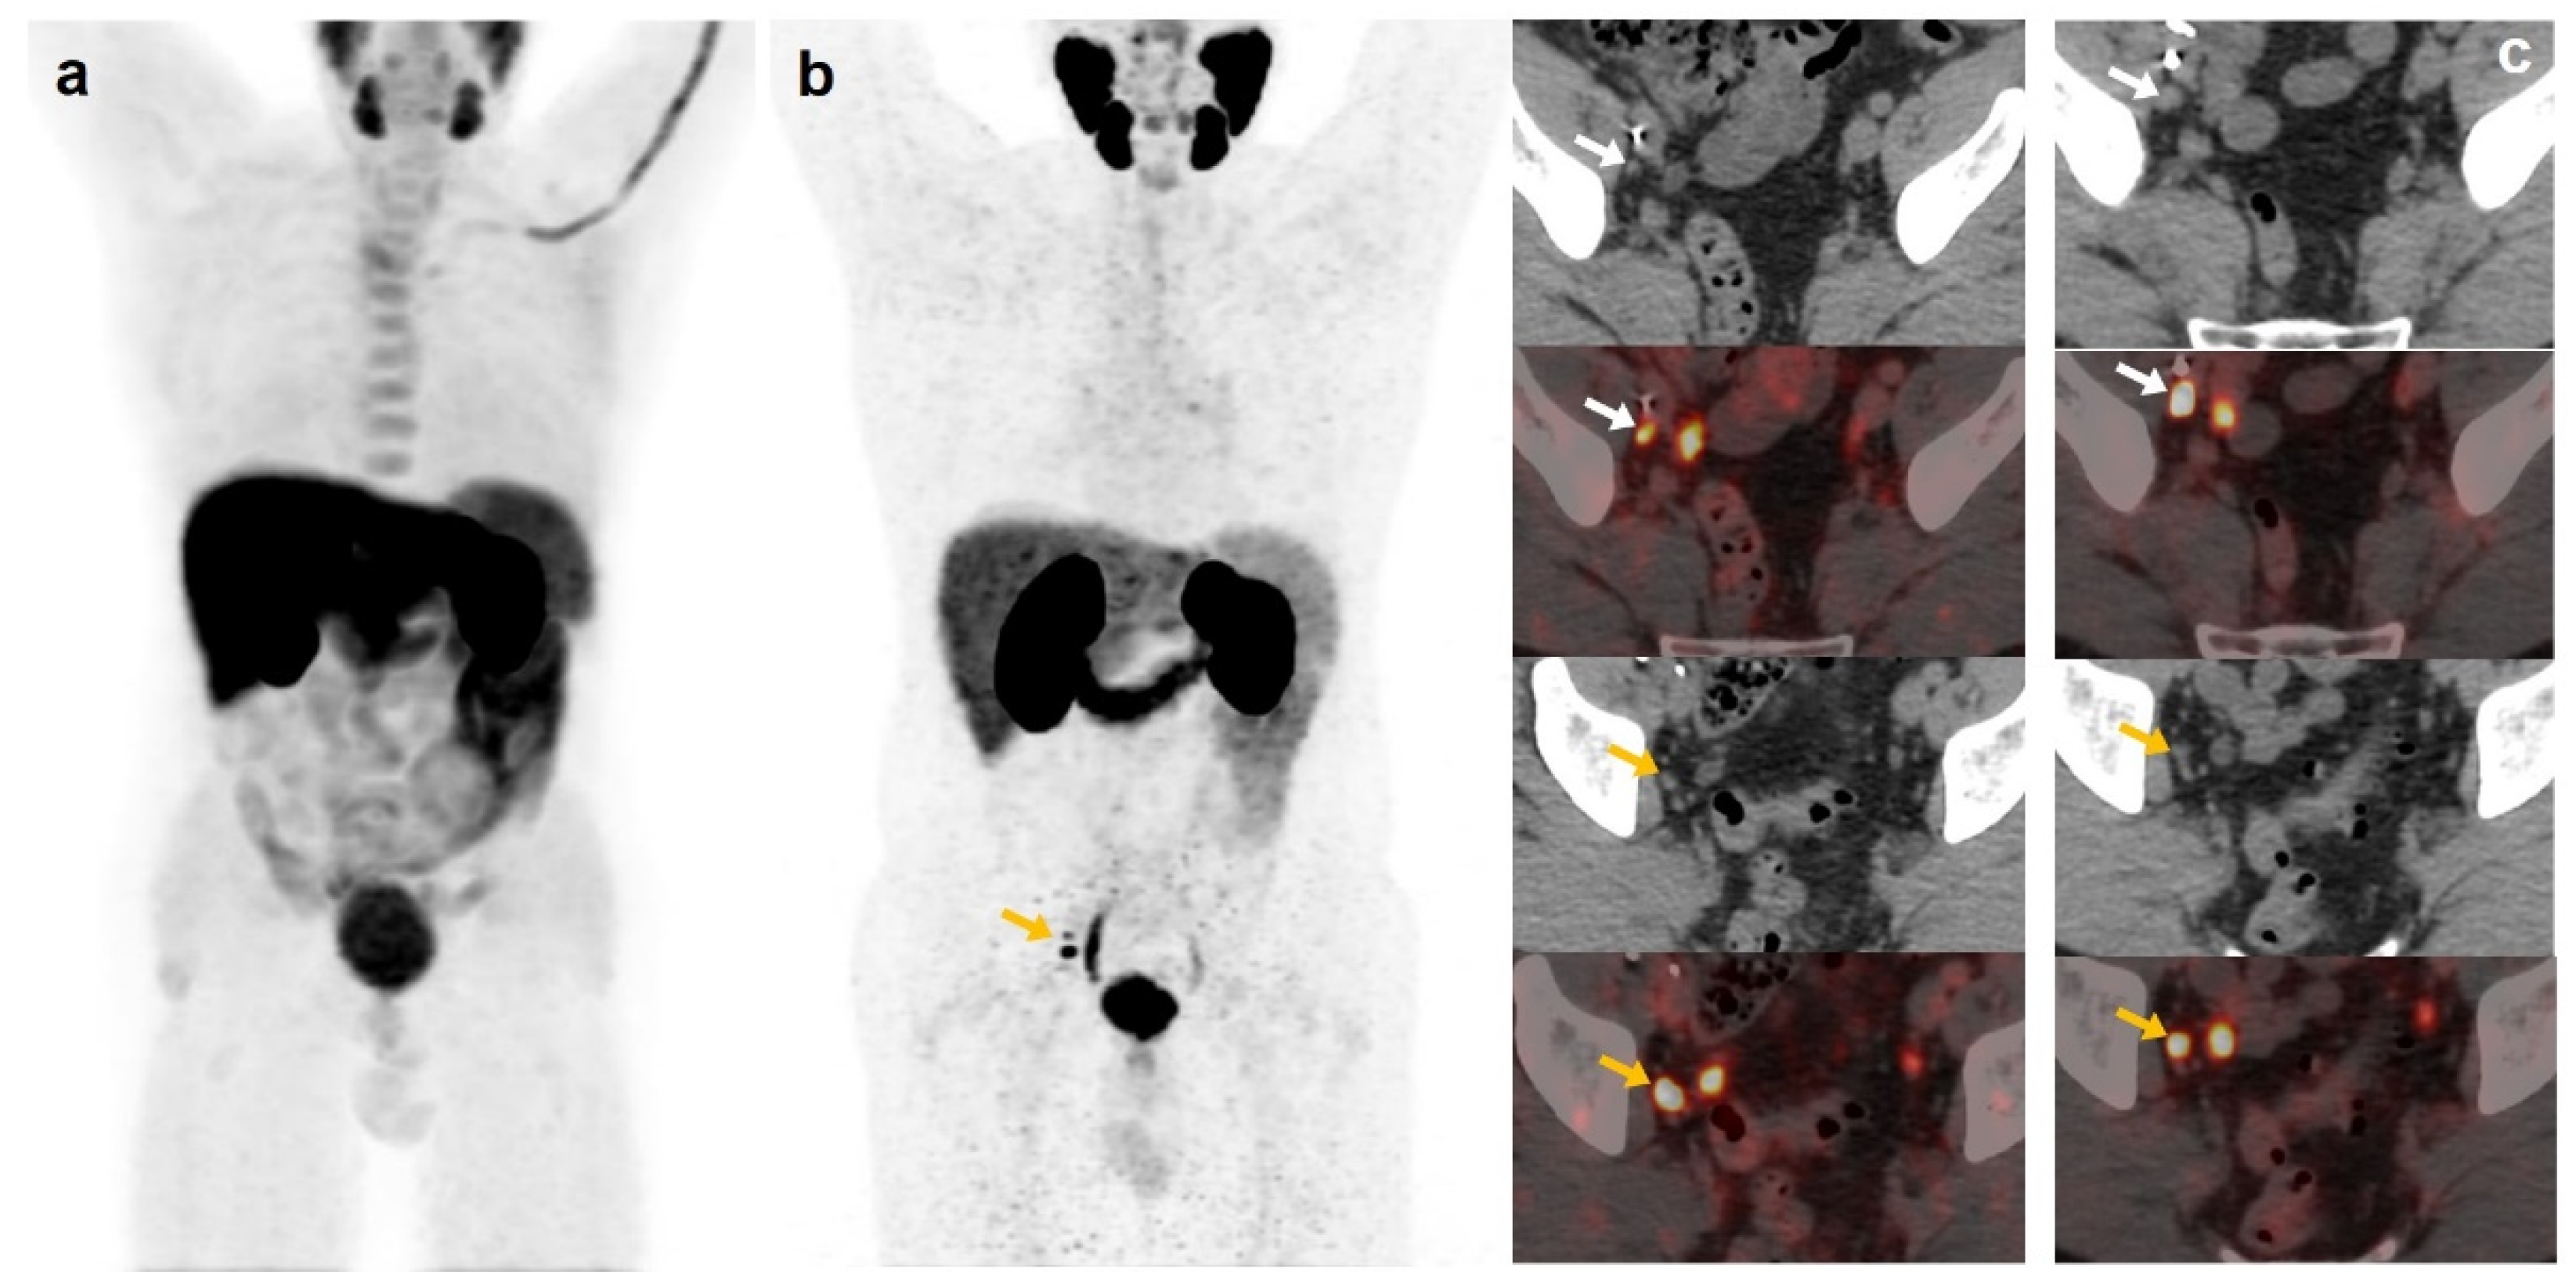

Derived from positive [18F]DCFPyL-PET/CT, 19 patients underwent additional diagnostic procedures to confirm the results: 8 by imaging (3/8 was confirmed) and 11 by histological analysis (8/11 was confirmed) (Figure 3 and Figure 4).

Figure 3.

55-year-old patient. Gleason 8 PCa treated with RP. First BCR treated with prostate fossa radiotherapy. Second BCR (PSA: 0.84 ng/mL, PSAdt 5.99 months, PSAvel 0.07 ng/mL/month). [18F]F-choline-PET/CT negative (a). [18F]DCFPyL-PET/CT (b), time window of twenty days, revealed two right external iliac lymph nodes metastases (white and yellow arrows). Lymphadenectomy was decided (escalation), without histopathological confirmation of malignancy. In follow-up, PSA progressed (2.07 ng/mL) and an additional [18F]DCFPyL-PET/CT (c) showed exactly same lymph nodes (white and yellow arrows). SBRT was administered decreasing the PSA level, reclassifying [18F]DCFPyL-PET/CT results as true positive.